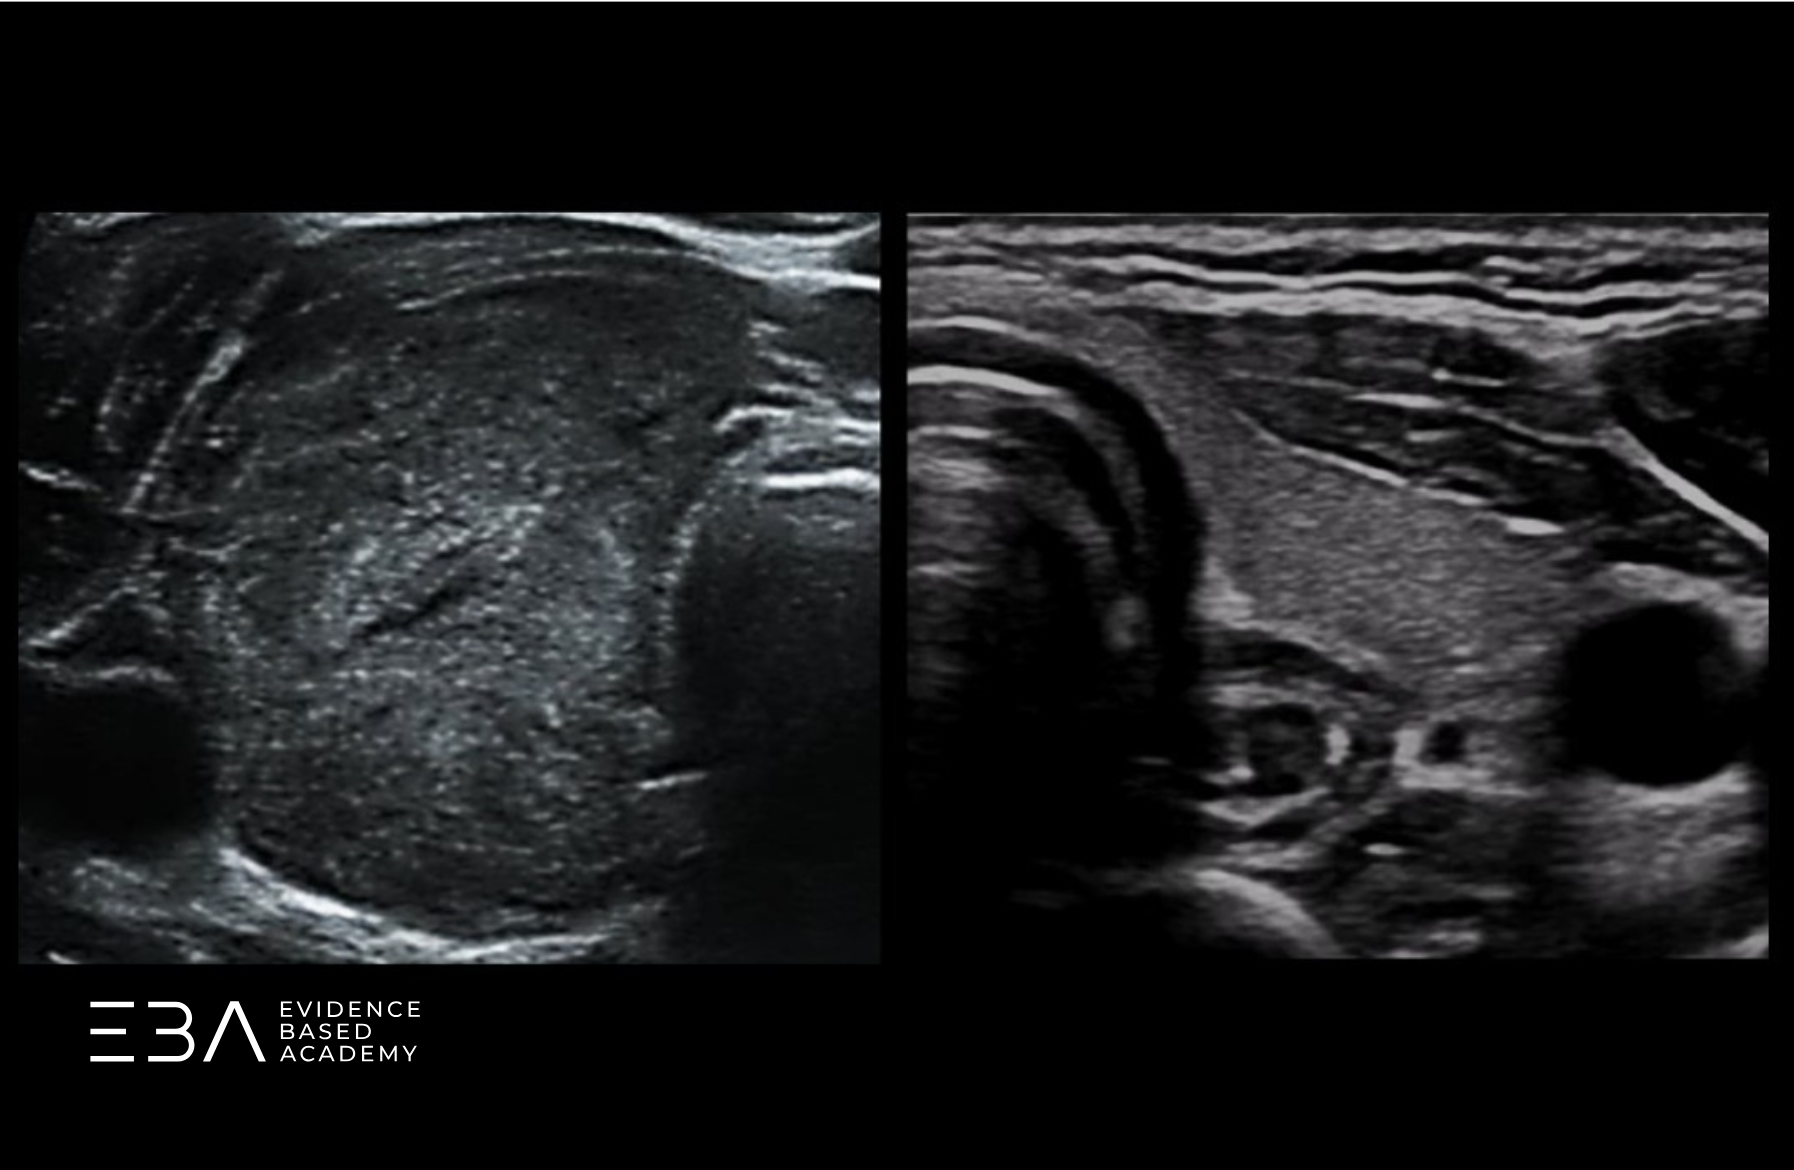

Warto zwrócić uwagę na strukturę położoną grzbietowo do tarczycy, zwykle po lewej stronie szyi. Przełyk, bo o nim mowa, w projekcji poprzecznej może początkowo imitować zmianę ogniskową. Zmiana projekcji na podłużną pozwala uwidocznić jego charakterystyczny kształt i rozwiać wątpliwości.

Przełyk w projekcji poprzecznej i podłużnej.